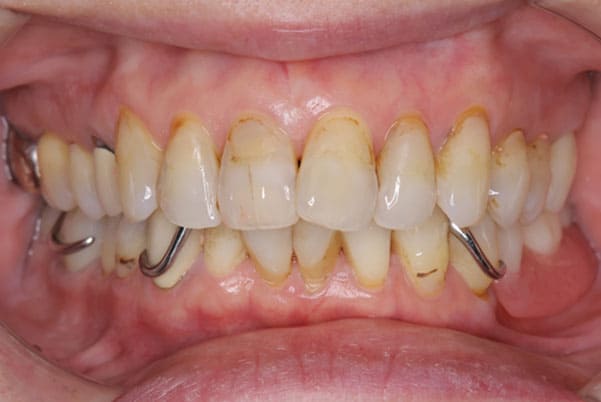

上の前歯が重度歯周病により動揺し、残せない状態のため、入れ歯も動揺がありました。

ご自身の歯に負担の少ないバネ、また見た目も改善

ご自身の歯に負担の少ないバネ

銀歯からセラミック歯に

バネをかける歯は繋げることで強度を増し、歯への負担を軽減し、歯の寿命を長くする設計へ。

バネがかかる歯の被せ物は、歯への負担を減らし、入れ歯が動きにくいようになる形態をあらかじめ付与することで、より入れ歯の機能が高まります。

治療を行う際、被せ物や入れ歯は、別々に考えるのではなく、一口腔単位としてお口全体のことを考え最良の治療計画を立てることが歯の寿命、機能効果を向上させるため、専門医としてこのことは常に心掛けて治療を行っています。

残りの歯に負担がかからないよう、被せ物と入れ歯の一体化を図った入れ歯

治療前は上下奥歯の入れ歯が削れていることで、かみ合わせが低くなり唇もつむった状態でした。

かみ合わせを適切な高さに戻したことで、本来の自然な口元へ。